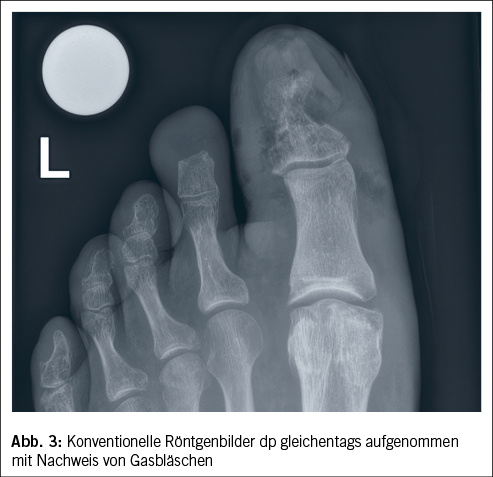

Ein Weichteilinfekt sollte anhand definierter klinischer Kriterien diagnostiziert werden (36). Bei Fehlen dieser klinischen Kriterien für eine Weichteilinfektion und bei Fehlen einer Osteomyelitis sollte auf die Gabe von Antibiotika verzichtet werden (37, 38). Der Verdachtsmoment einer Osteomyelitis kann durch die Kombination eines positiven «Probe-to-Bone-Test» (d.h. direkter Knochenkontakt einer durch die Wunde eingeführten sterilen Metallsonde), erhöhter laborchemischer Entzündungswerte sowie typischer Veränderungen in konventionellen Röntgenaufnahmen gestellt werden (36). Die Magnetresonanztomographie hat eine hohe Sensitivität in der Diagnostik einer Osteomyelitis (39) und dient bei der chirurgischen Planung in der präoperativen Bestimmung der Ausdehnung der Knochenbeteiligung (40). Zur Bestimmung des Schweregrades der Infektion wird die IWGDF/IDSA-DFI-Klassifikation empfohlen (36). Schwere Infektionen (d.h. alle Infektionen, die mit dem Vorhandensein von zwei oder mehr SIRS-Zeichen einhergehen) und moderate Infektionen (d.h. mehr als 2 cm Erythem um das DFU herum und/oder Gewebe tiefer als Haut und Subkutangewebe betroffen) mit relevanten Begleiterkrankungen wie schwere pAVK, Immunsuppression oder terminale Niereninsuffizienz sollten stationär behandelt werden (36). Ohne Knochenbeteiligung besteht die Therapie aus einem lokalen Debridement des infizierten Gewebes und einer Antibiotikatherapie von 1–2 Wochen nach Probenentnahme (36). Bei Nachweis einer Osteomyelitis kann zwischen einer konservativen Therapie (Antibiotika über 6 Wochen) und einer Entfernung des befallenen Knochens (was oftmals eine Amputation nach sich zieht, seltener eine innere Resektion nur des befallenen Knochens, bei der nur der infizierte Knochen entfernt wird [41]) abgewogen werden. Gasbildende Infekte, ausgedehnte Weichteilschäden, stark kompromittierte periphere Durchblutungsverhältnisse und Patientenfaktoren, die gegen eine 6 Wochen andauernde Antibiotikatherapie sprechen, lassen die Amputation bevorzugen. Insbesondere akrale Osteomyelitiden können erfolgreich konservativ therapiert werden (42). In naher Zukunft werden die Ergebnisse einer schweizerischen monozentrischen prospektiv-randomisierten Studie erwartet, im Rahmen derer die Antibiotikatherapiedauer bei diabetischen Fussinfektionen drastisch reduziert wurde (43). Das unter Abbildung 1–4 gezeigte Fallbeispiel zeigt einen 47 Jahre alten Patienten mit schlechter Adhärenz zur Entlastungstherapie mit dem Vollbild einer gasbildenden diabetischen Fussosteomyelitis, der septisch während der Nacht auf unserer Notfallstation vorstellig wurde. Die Therapie bestand in einer sofortigen Grosszehenamputation.